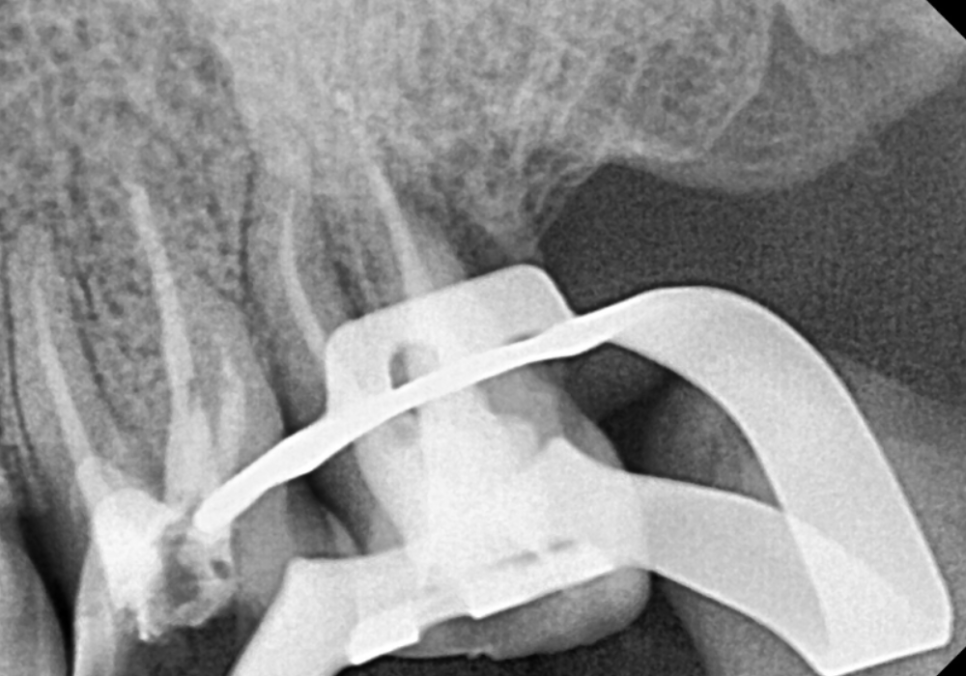

뽑고 난 뒤 치아를 직접 살펴보니,

사진처럼 뿌리 끝까지 수직으로

선명하게 파절된 선이 보였어요.

겉으로는 보이지 않던 깊은 곳에서

이미 치아가 완전히 갈라져 있었던 것이죠.